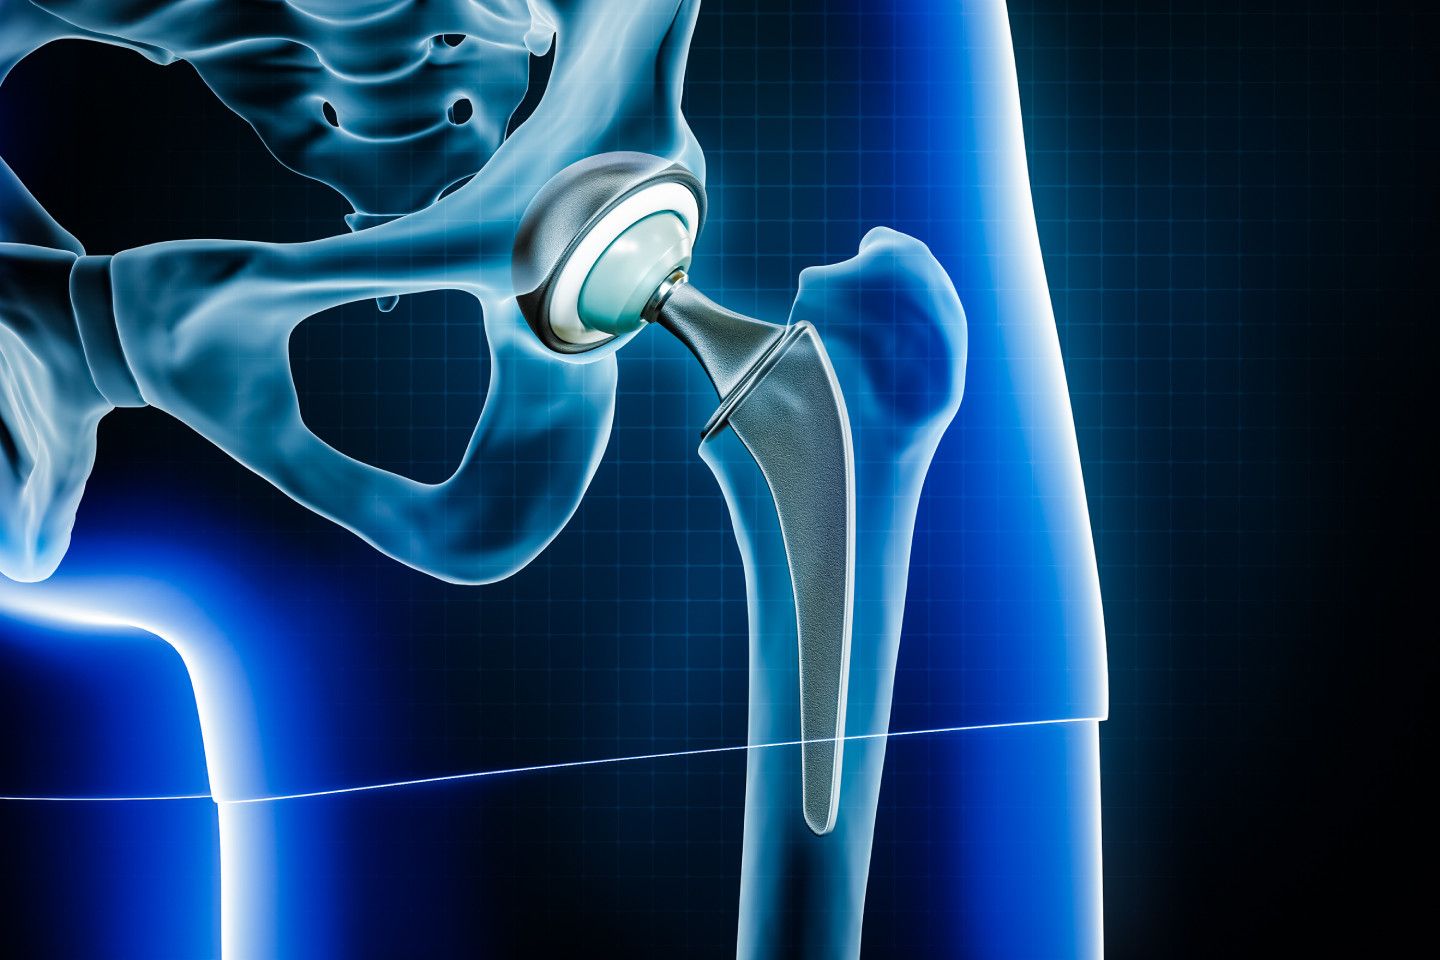

Hip Replacement Surgery (also called Total Hip Arthroplasty) is performed when the hip joint is badly damaged often due to arthritis, an old injury, or natural wear and tear. The damaged parts of the hip are removed and replaced with an artificial joint made from metal, ceramic, or medical-grade plastic. The goal is simple to restore movement and relieve pain that no longer responds to medicine or physiotherapy. Over the years, Total Hip Replacement Surgery in Jaipur has helped thousands of patients walk without pain, climb stairs comfortably, and return to an active lifestyle. It’s now considered one of the most successful orthopedic procedures worldwide.

On the day of the procedure, anesthesia is administered to keep you comfortable. The surgeon then removes the damaged portion of the hip joint and replaces it with an artificial implant. In advanced hospitals, Robotic Hip Replacement Surgery in Jaipur is now available. This technology uses 3D imaging to create a digital model of your hip, allowing the surgeon to plan each step precisely. The robotic system helps in achieving perfect implant placement, smaller incisions, and quicker recovery. The entire process usually takes two to three hours. After the surgery, you’ll be monitored closely before being moved to your hospital room.